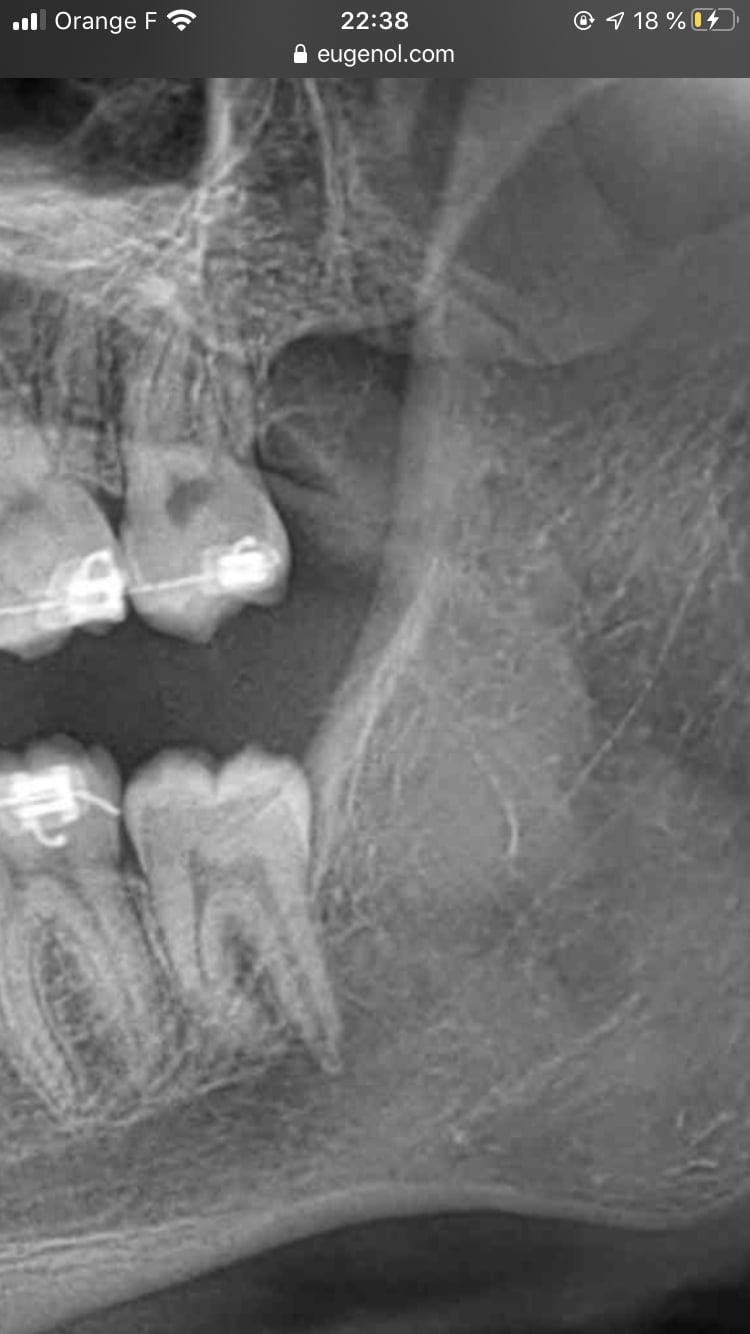

Une ortho me demande de procéder à l'extraction de la 47 sur un enfant de presque 18 ans.

1 - oui il n'est pas possible de redresser ce genre de dent ?

2 - de toutes façons, y'a pas la place pour que cette dent soit correctement en place en particulier au niveau gingival.

A côté de ça, redresser la dent ok, et ensuite ? Quelle place disponible ? Regardez la 37, elle est bien dans l'axe, et pourtant son arrivée sur l'arcade semble incertaine aussi par manque de place ! Redresser c'est bien beau mais s'il n'y a pas la place de toutes façons...

Bref, le plus simple reste d'en parler directement avec l'ortho. Il a vu le patient en bouche, il a d'autres documents que juste une pano (et encore bravo à ceux ici qui arrivent à faire un plan de traitement avec juste ça, moi j'en suis bien incapable), il pourra t'expliquer les raisons de son choix.

Je ne vois pas comment on pourrait mettre tout ce petit monde en place sur l'arcade proprement. Là au mieux tu vas finir avec la face distale de 37 et 47 sous un capuchon muqueux, à moitié bloqué par la branche montante de la mandibule, ça va juste générer des abcès comme une dent de sagesse mal sortie et au bout du compte une belle carie sur une dent qui sera bien difficilement restaurable par le dentiste puisqu'à moitié dans la gencive.

37 a déjà limite la place , propice pour avoir des péricoronarites.

47 si bien remise en place : même sanction. Et encore sacrée galère pour la mettre comme il faut en occlusion avec 17. À extraire

Il y aura exactement le même espace que pour sa 37 . Avec en D un beau fourre-tout propice aux pericoronarites. Même pas besoin de voir en clinique ce qu’il se passe . On voit bien la portion osseuse en D de 37 qui longe la dent. Avec une sonde paro on doit y enfoncer l’équivalent d’1 cm.

Totalement d’accord avec Doagui , faut comparer ce qui est comparable. Quant à l’histoire de la branche montante qui est en V par rapport à l’arcade ....... il y a juste à regarder la lamina dura qui se prolonge en D de la 7 pour comprendre qu’on a 1 cm de fausse poche favorable à la mise en place de plaque dentaire propice à une inflammation carabinée gingivale que le patient ne pourra JAMAIS nettoyer sans l’intervention d’un insert à détartrer. Dans ton cas Dancha le patient peut nettoyer la zone . Dans l’autre cas il est tout bonnement impossible de nettoyer la zone.